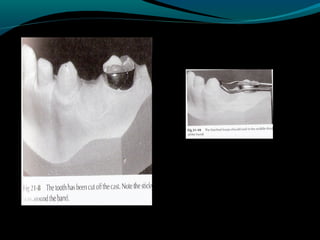

DISTAL SHOE

(Intra-alveolar,Eruption guidance

appliance)

o Used to maintain the space of a primary

second molar that has been lost before

the eruption of the permanent first

molar.

o An unerupted permanent first molar

drifts mesially within the alveolar bone if

the primary second molar is lost

prematurely.The result of the mesial

drifts is loss of arch length & possible

impaction of the second premolar.

DISADVANTAGES-

o Because of its cantilever design & the fact it is

anchored on the occlusally convergent crown of

the primary first molar,the appliance can replace

only a single tooth & is somewhat fragile.

o No occlusal function is restored because of this

lack of strength.